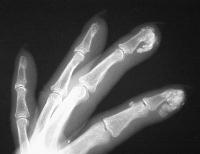

Healing ulcerations on the left index and middle fingertips, where calcium deposits have spontaneously drained in the past.